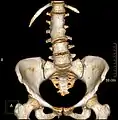

Congenital anomalies

Congenital vertebral anomalies can cause compression of the spinal cord by deforming the vertebral canal or causing instability.